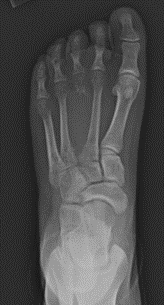

X-ray of a 15-year-old female with a destructive bone lesion to the third metatarsal.

X-ray of the 15-year-old female's left foot 6 months after surgery with curettage and bone grafting show a healing ABC. The patient is back to all activities and is pain free.